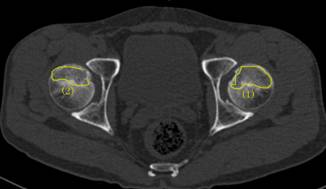

術(shù)前報告顯示患者雙側(cè)股骨頭壞死

37歲的患者吳先生反復(fù)雙髖疼痛2月余,聽說瀘州市中醫(yī)院在治療骨科疾病方面很有經(jīng)驗,遂來到醫(yī)院治療。經(jīng)檢查,吳先生雙側(cè)股骨頭壞死(II期),如不及時進行手術(shù)治療,他的股骨頭將進一步壞死至骨頭塌陷,引發(fā)關(guān)節(jié)炎,嚴(yán)重時,必須行關(guān)節(jié)置換術(shù)。這樣,將會給吳先生的生活質(zhì)量及經(jīng)濟帶來嚴(yán)重負(fù)擔(dān)。